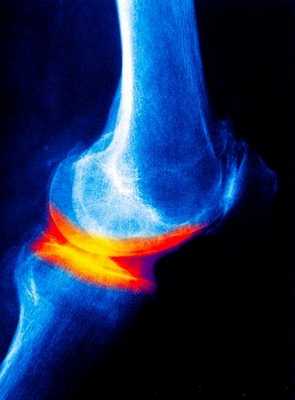

Гонартроз протекает, как правило, более благоприятно, чем коксартроз. Обычно гонартроз бывает вторичным, связан с травмой сустава или статическим.Симптоматика проявляется болями с внутренней или передней части коленного сустава, боли возникают при ходьбе (наиболее сильно при подъеме по лестнице).Кроме того возникает хруст при интенсивных движениях, в суставе появляется нестабильность сустава. Кроме того, возможна скованность в суставе в утренние часы с регрессом в течение 30 минут.